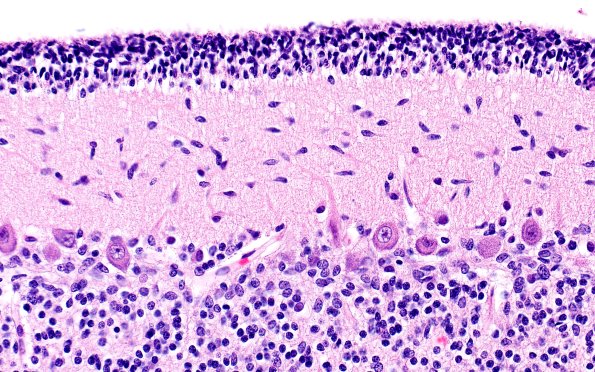

Washington University Experience | METABOLIC | Menkes disease | 4B3 Menkes Dz (Case 4) H&E 40X

There are no substantial dysmorphic changes in the dendritic Purkinje cell arbor comparable to other cases of Menkes disease shown in this atlas. (H&E)